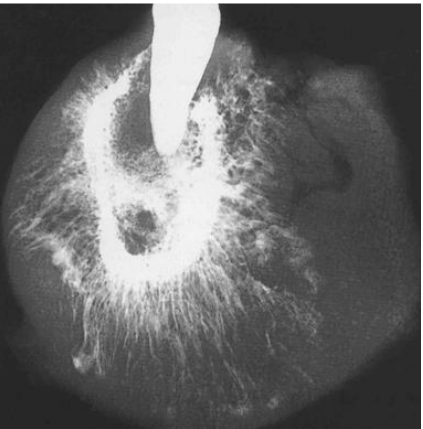

76. 此種放射線影像檢查的結果,其最可能的診斷為何?

(A)Mandibular fracture (B)Maxillary palatine cyst (C)Maxillary sinusitis (D)Fibrous dysplasia

79. 黑色箭頭所指為何? (A)骨膜反應(periosteal bone reaction) (B)腐骨(sequestra) (C)腫瘤團塊(tumor mass) (D)軟組織鈣化(soft tissue calcification)

80.承上題,白色箭頭所指為何? (A)人為影像重疊(double image artefact) (B)骨膜反應(periosteal bone reaction) (C)鈣化血管(calcified vessel) (D)腐骨(sequestra)